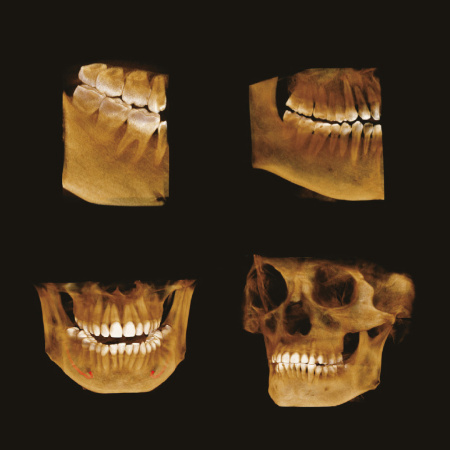

Возможности 3D КТ

Расширенные возможности сканирования

PAPAYA 3D удовлетворит потребности врачей всех специальностей от эндодонтов до ортодонтов и даже пластических хирургов.

PAPAYA 3D подходит для сканирования головы и даже шеи. Аппарат предназначен для широкого применения в различных областях, начиная от планирования отдельных зубных имплантатов с малой областью сканирования и заканчивая исследованием всего черепа с очень большой областью сканирования.

Широкая область сканирования ВНЧС

3D КТ – технологии высокого разрешения в Компьютерной Томографии

Зоны сканирования и функционал позволяющие поставить правильный диагноз даже в самых сложных клинических случаях.

Возможности 3D КТ

Расширенные возможности сканирования

PAPAYA 3D удовлетворит потребности врачей всех специальностей от эндодонтов до ортодонтов и даже пластических хирургов.

PAPAYA 3D подходит для сканирования головы и даже шеи. Аппарат предназначен для широкого применения в различных областях, начиная от планирования отдельных зубных имплантатов с малой областью сканирования и заканчивая исследованием всего черепа с очень большой областью сканирования.

Широкая область сканирования ВНЧС

3D КТ – технологии высокого разрешения в Компьютерной Томографии

Зоны сканирования и функционал позволяющие поставить правильный диагноз даже в самых сложных клинических случаях.